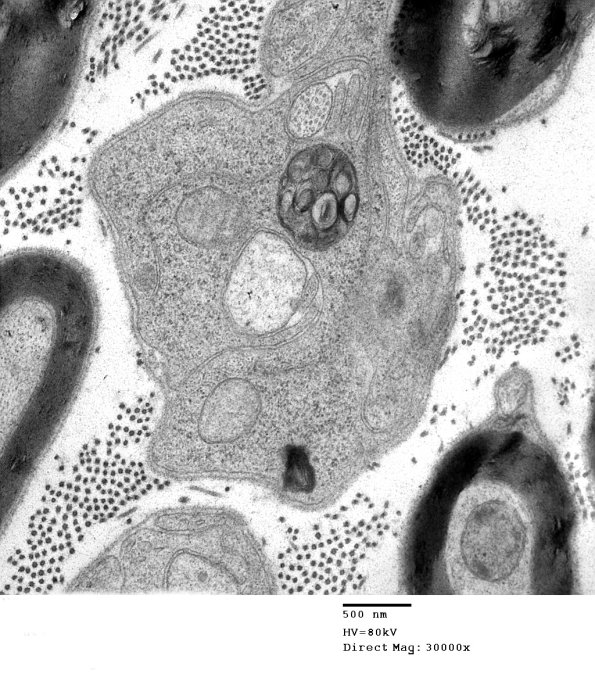

3B5 AMPK KO Mouse Degen Axons_022.jpg

3B5,6 Organelles shrink and darken making contents difficult to appreciate.